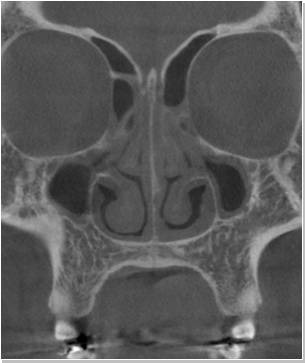

코재수술 CT 전후사진

비염

비중격만곡증

축농증